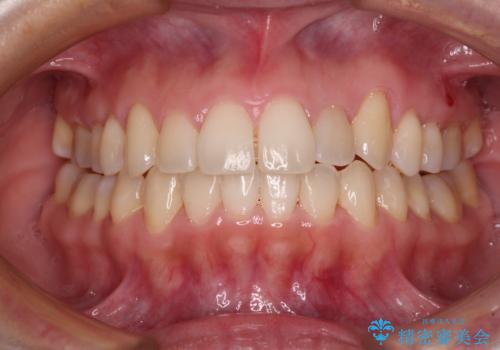

目立つ八重歯を治したい インビザラインによる矯正治療

ディープバイトとデコボコを解消 インビザライン矯正

デコボコとディープバイトを治したい インビザラインによる矯正治療

前歯のがたつき 深い噛み合わせを改善したい